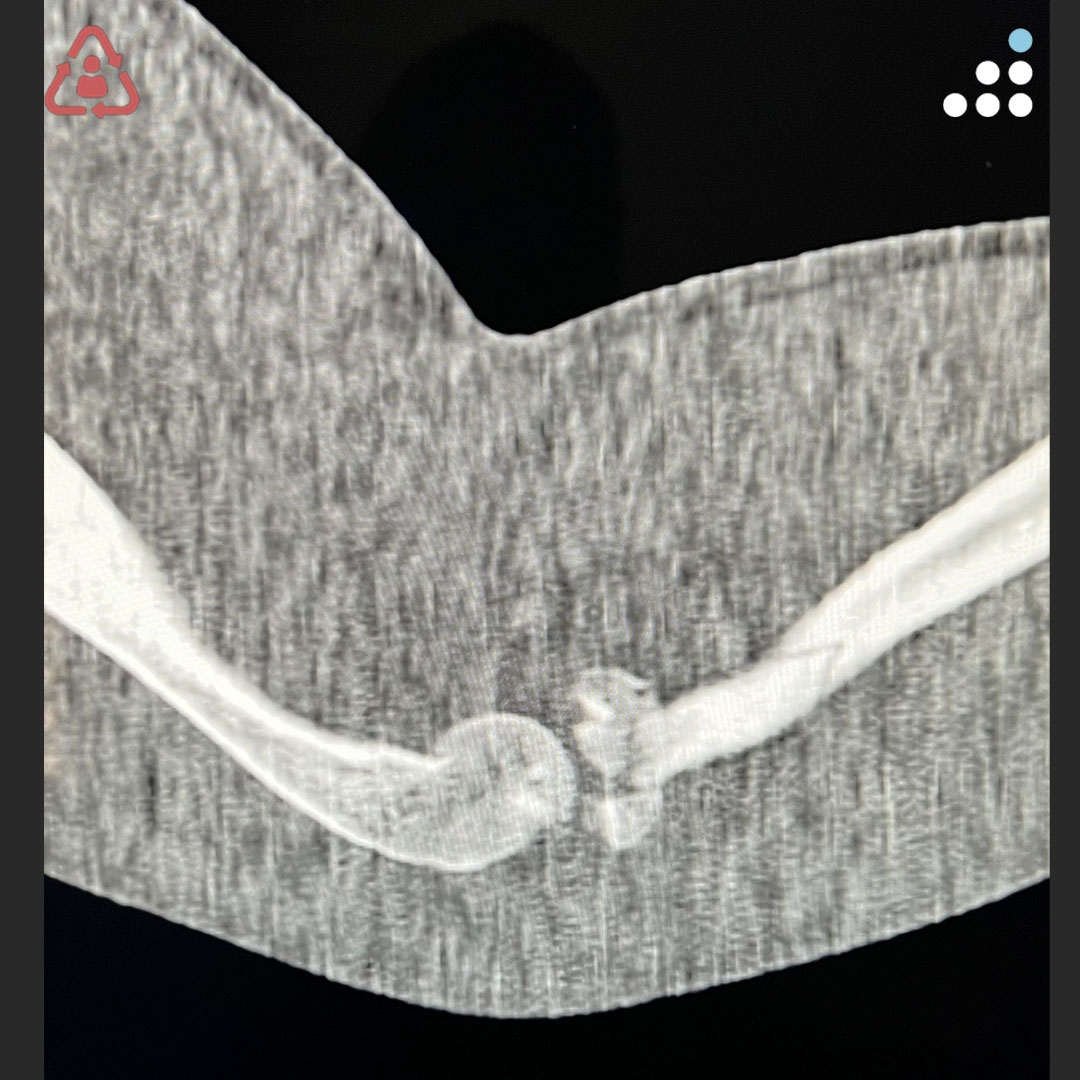

@orthobullets @KPSCALnews @rkh_md @DrMarecek @DeformityDoc @jamesablairMD @FractureDoc @stevemchale @traumaticum @DrFraneNicholas I am concerned about the +Fleck/flake sign. Get MRI or ultrasound to rule out a triceps rupture. If torn, I would perform ORIF and Triceps repair, after restoring the underlying metabolic issues. If the triceps is not torn, then would treat non-operatively.